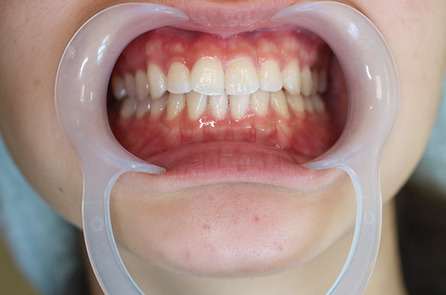

1矯正・マウスピース【治療例1】

治療前

治療後